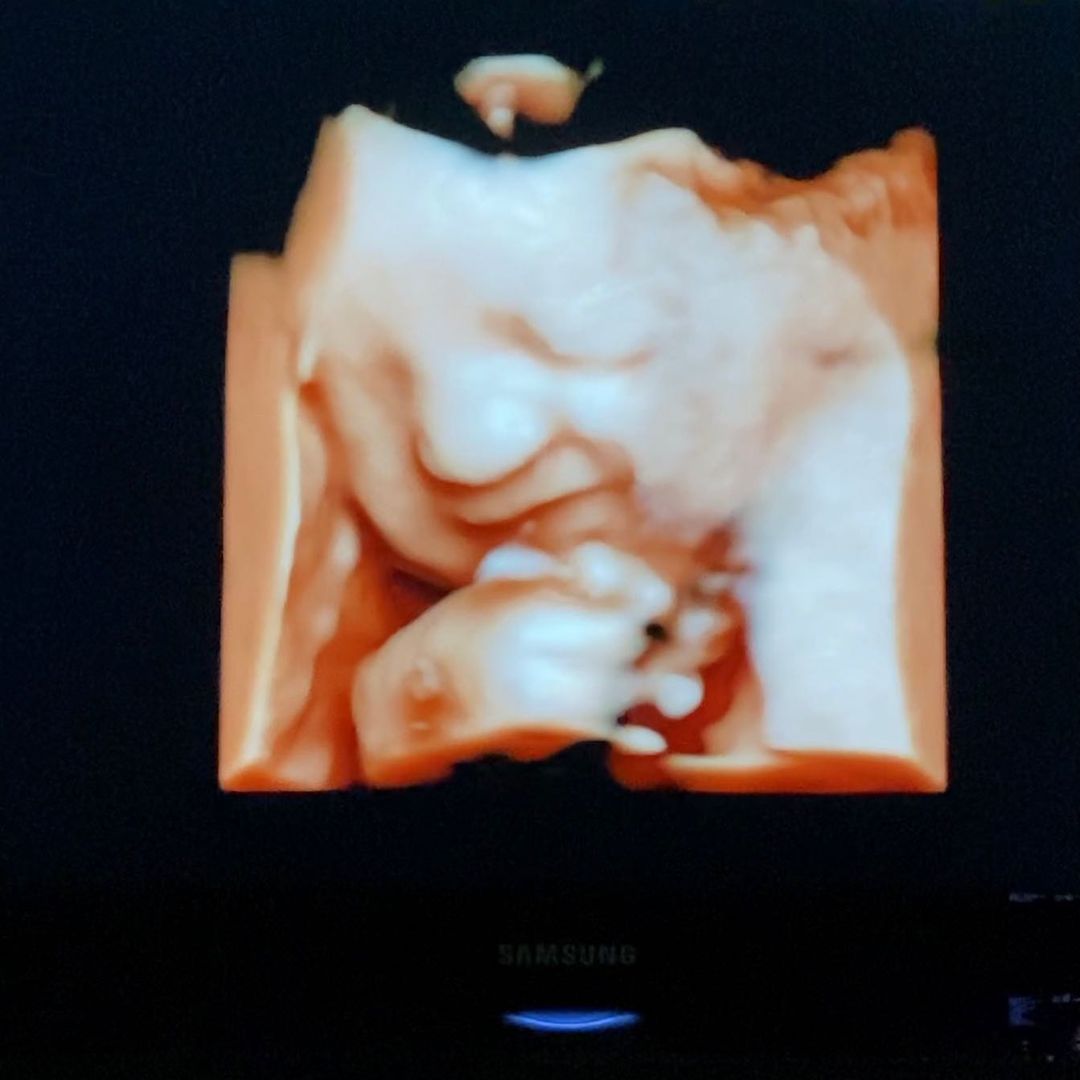

แกลเลอรีรูปภาพ "หยาดทิพย์" แข็งแรงมาก อีกไม่ถึงเดือนได้เจอหน้าลูกสาวแล้ว

22 ภาพ "หยาดทิพย์" แข็งแรงมาก อีกไม่ถึงเดือนได้เจอหน้าลูกสาวแล้ว